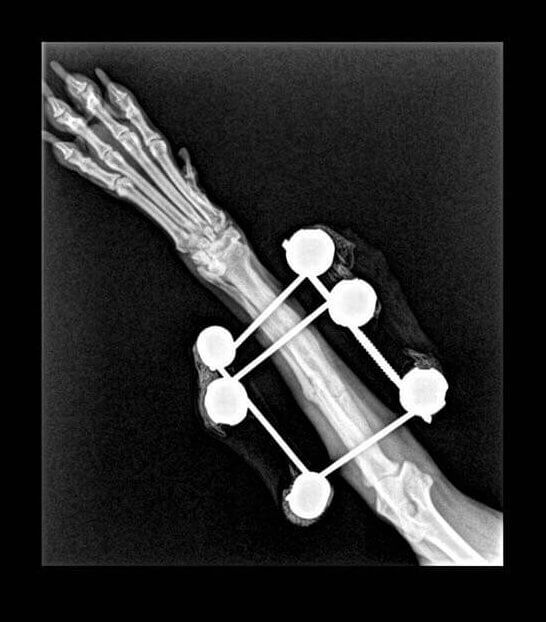

Atès que tot l’examen físic general era normal, li vam realitzar una radiografia. Tal com el propietari s’imaginava, Lluna tenia una fractura a nivell de la diàfisi mitjana del cúbit i el radi (avantbraç).

En aquest cas es va decidir utilitzar uns fixadors externs per donar estabilitat a l’articulació ja que els teixits al voltant de la zona de fractura estaven inflamats i podrien donar problemes de cicatrització si s’hi havia d’incidir per col·locar una placa d’osteosíntesi.

En les següents revisions es va observar molt bona evolució i consolidació òssia de la fractura fins que es va decidir retirar els implants perquè Luna ja pogués fer vida normal.